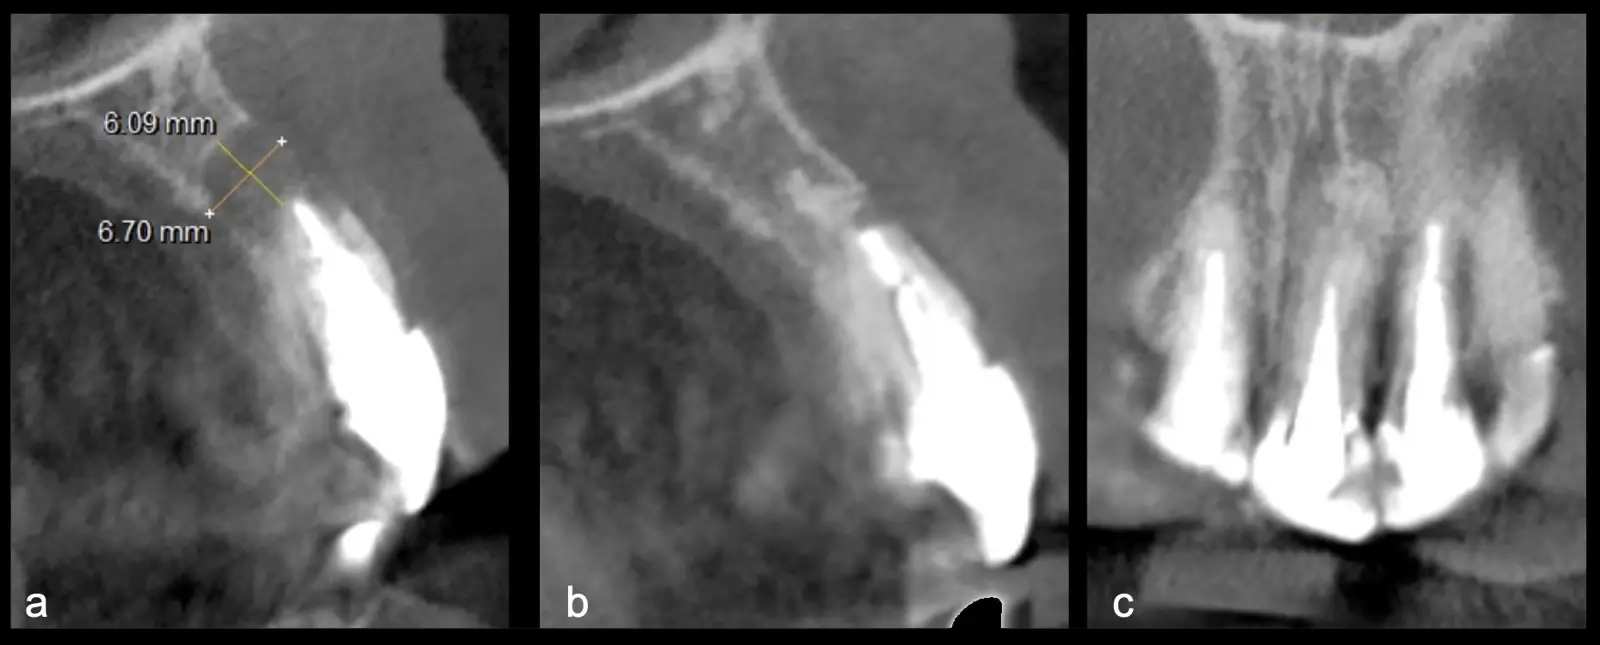

Paciente de sexo femenino de 46 años, llega a la consulta por presentar odontalgia en la pieza 2.1. Al examen clínico se observa restauración coronaria con ausencia de movilidad dentaria y la paciente refiere dolor a la percusión vertical. En la evaluación tomográfica se observó tratamiento de conducto radicular y espigo intrarradicular acompañado de imagen hipodensa a nivel apical compatible con proceso infeccioso crónico. Se procede a realizar apicectomía mediante técnica por desgaste, finalizando con la preparación y obturación de conducto radicular apical por vía retrógrada.

Figura 24. Vista sagital TCCB pieza 2.1. Preoperatorio: imagen hipodensa de 6 mm de diámetro con osteólisis y pérdida de tabla vestibular y palatina (a). Control a los 3 años: imagen hiperdensa compatible con zona regenerada a nivel apical, con presencia de cortical palatina y vestibular (b). Vista coronal TCCB pieza 2.1 control a los 3 años: imagen hiperdensa compatible con hueso en proceso de reparación, presencia de cortical palatina y vestibular (c).